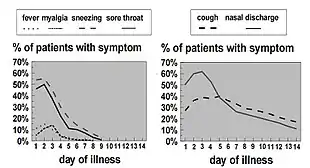

The typical symptoms of a cold include cough, runny nose, sneezing, nasal congestion, and a sore throat, sometimes accompanied by muscle ache, fatigue, headache, and loss of appetite.[21] A sore throat is present in about 40% of cases, a cough in about 50%,[8] and muscle ache likewise in about 50%.[4] In adults, a fever is generally not present but it is common in infants and young children.[4] The cough is usually mild compared to that accompanying influenza.[4] While a cough and a fever indicate a higher likelihood of influenza in adults, a great deal of similarity exists between these two conditions.[22] A number of the viruses that cause the common cold may also result in asymptomatic infections.[23][24]

A cold usually begins with fatigue, a feeling of being chilled, sneezing, and a headache, followed in a couple of days by a runny nose and cough.[21] Symptoms may begin within sixteen hours of exposure[26] and typically peak two to four days after onset.[4][27] They usually resolve in seven to ten days, but some can last for up to three weeks.[7] The average duration of cough is eighteen days[28] and in some cases people develop a post-viral cough which can linger after the infection is gone.[29] In children, the cough lasts for more than ten days in 35–40% of cases and continues for more than 25 days in 10%.[30]